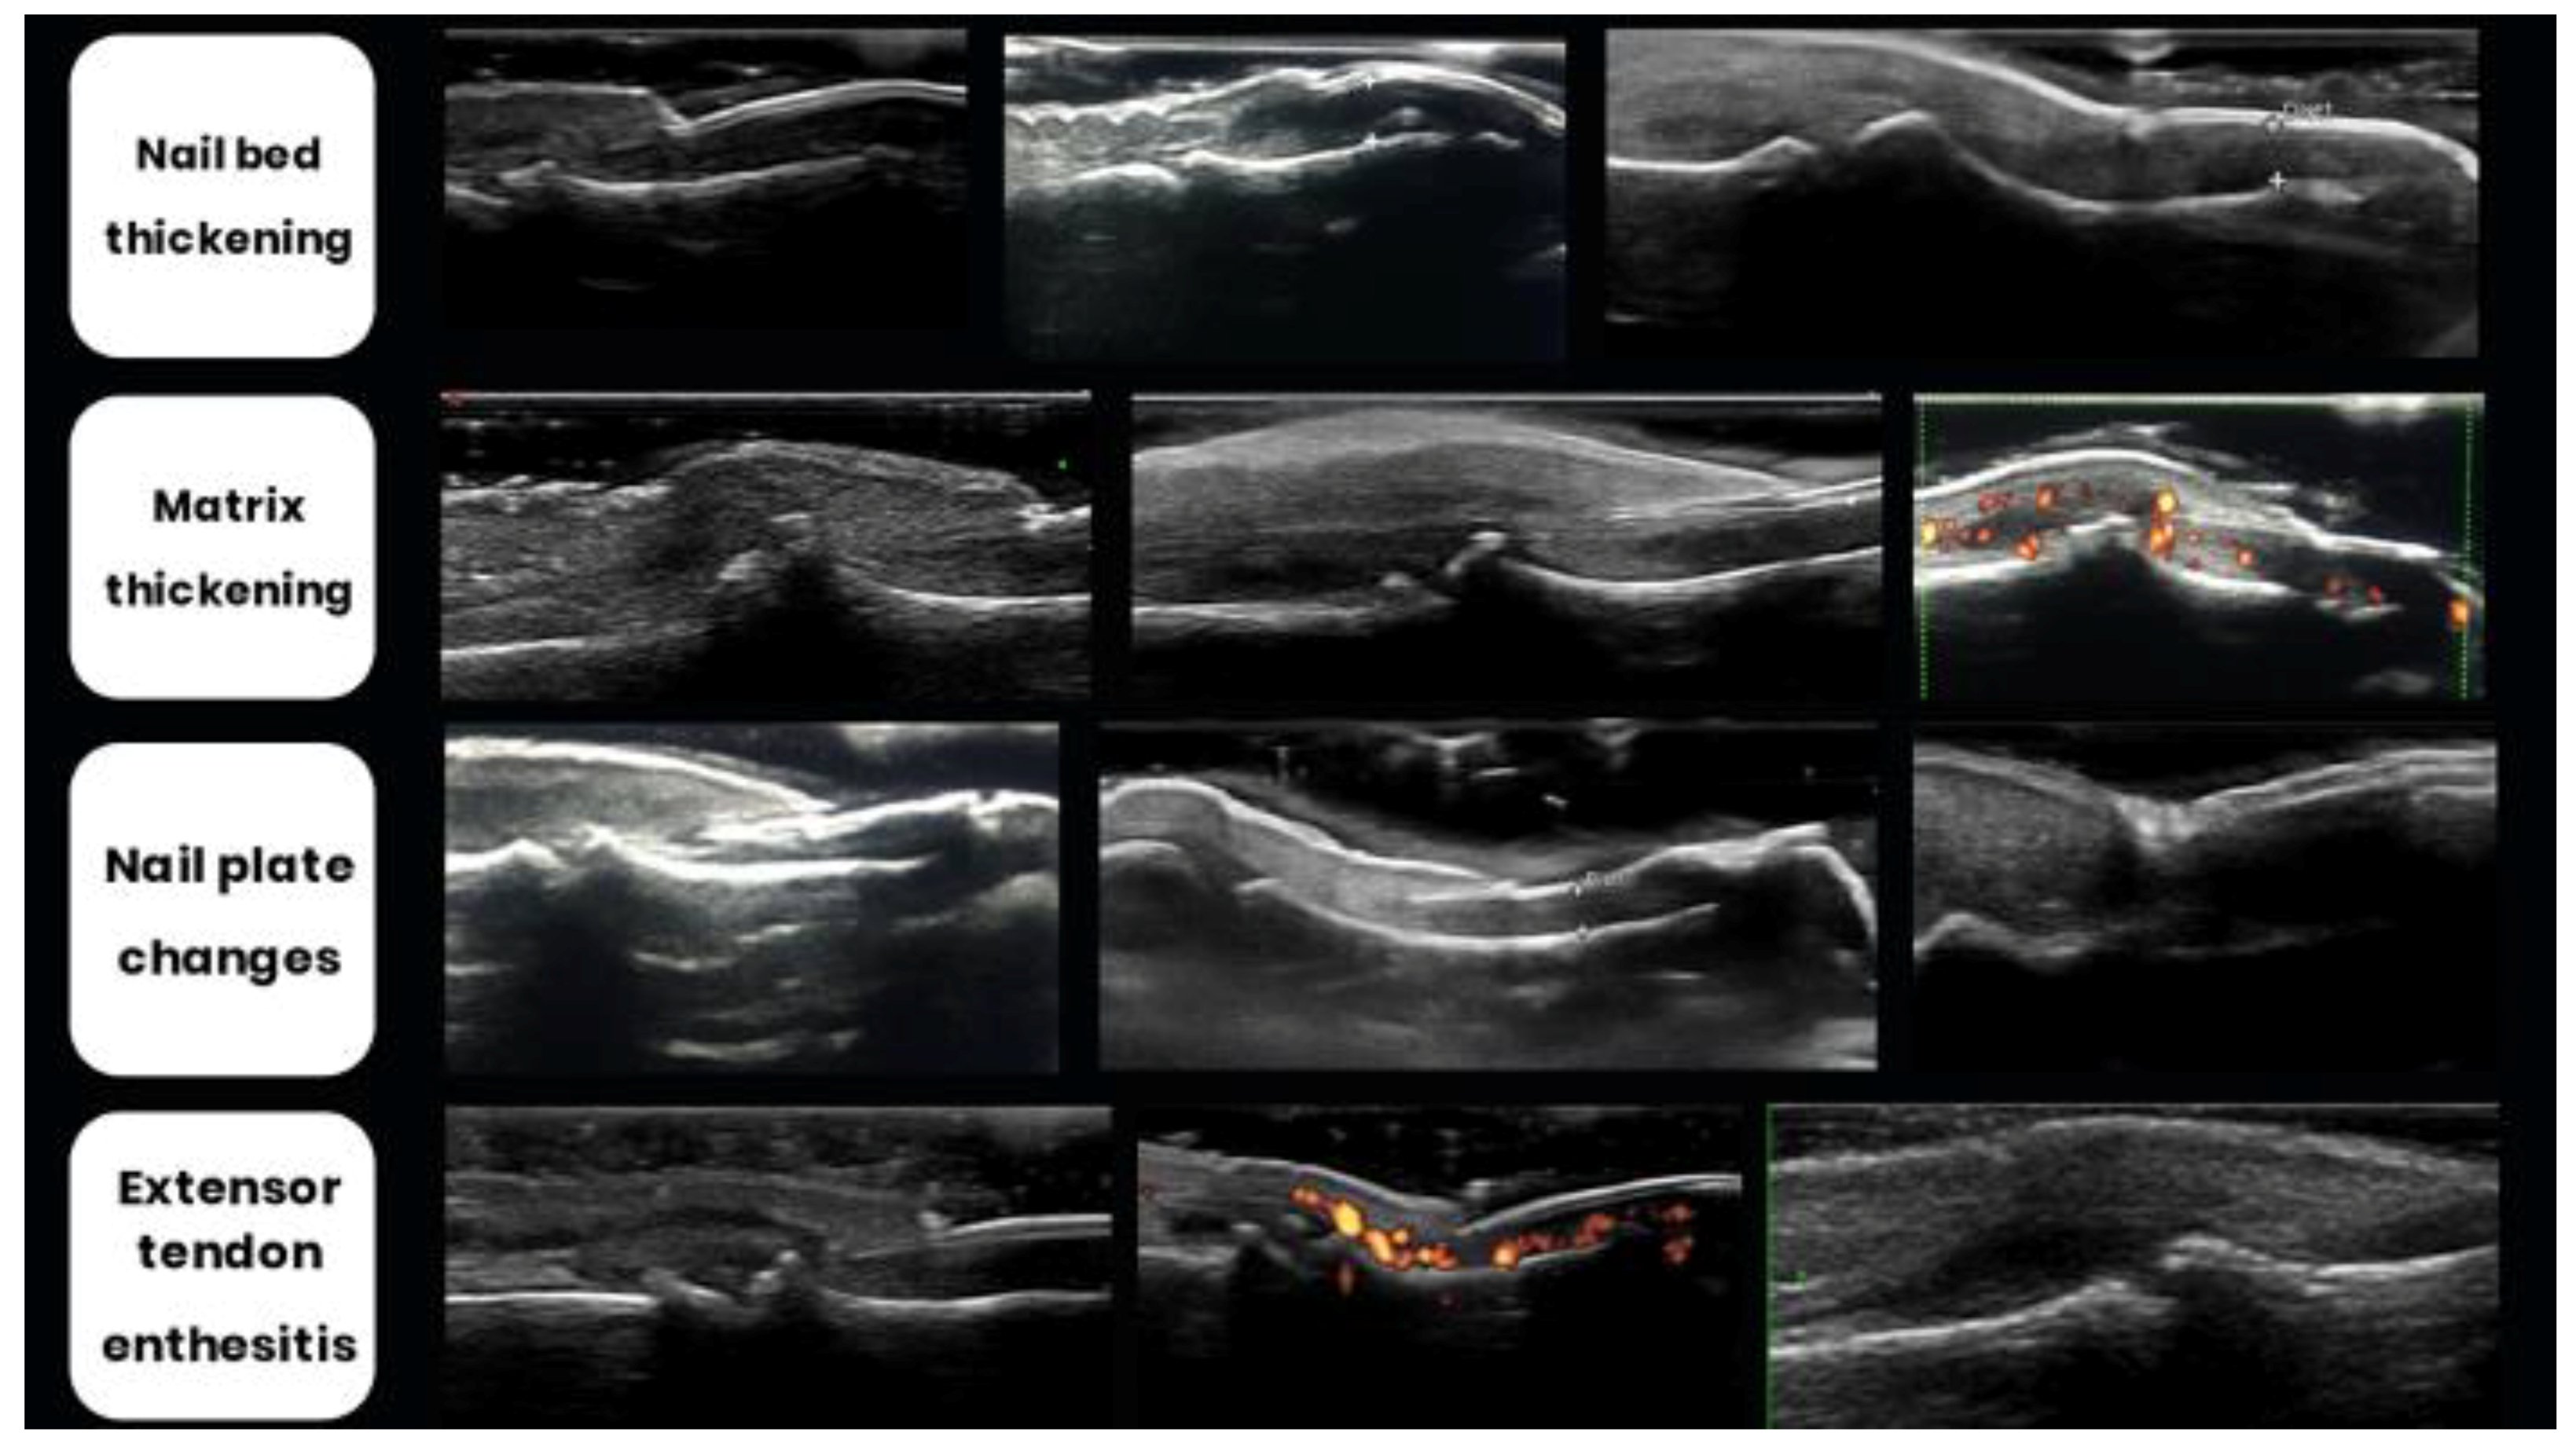

2.7. Nail Changes

- Acosta-Felquer, M.L.; Ruta, S.; Rosa, J.; Marin, J.; Ferreyra-Garrot, L.; Galimberti, M.L.; Galimberti, R.; Garcia-Monaco, R.; Soriano, E.R. Ultrasound entheseal abnormalities at the distal interphalangeal joints and clinical nail involvement in patients with psoriasis and psoriatic arthritis, supporting the nail-enthesitis theory. Semin. Arthritis Rheum. 2017, 47, 338–342. [Google Scholar] [CrossRef]

- Batticciotto, A.; Idolazzi, L.; De Lucia, O.; Tinazzi, I.; Iagnocco, A. Could nail and joint alterations make the difference between psoriatic arthritis and osteoarthritis during the ultrasonographic evaluation of the distal interphalangeal joints? Med. Ultrason. 2017, 19, 347–348. [Google Scholar] [CrossRef]

- Tan, A.L.; Benjamin, M.; Toumi, H.; Grainger, A.J.; Tanner, S.F.; Emery, P.; McGonagle, D. The relationship between the extensor tendon enthesis and the nail in distal interphalangeal joint disease in psoriatic arthritis--a high-resolution MRI and histological study. Rheumatology 2007, 46, 253–256. [Google Scholar] [CrossRef]

- Wortsman, X. Ultrasound in Dermatology: Why, How, and When? Semin. Ultrasound CT MRI 2013, 34, 177–195. [Google Scholar] [CrossRef] [PubMed]

- Cecchini, A.; Montella, A.; Ena, P.; Meloni, G.B.; Mazzarello, V. Ultrasound anatomy of normal nails unit with 18 MHz linear transducer. Italy J. Anat. Embryol. 2009, 114, 137–144. [Google Scholar]

- Wortsman, C.X.; Holm, E.A.; Jemec, G.B.; Gniadecka, M.; Wulf, H.C. Ultrasonido De Alta Resolucion (15 MHz) en el Estudio de la Uña Psoriatica. Rev. Chil. Radiol. 2004, 10, 06–11. [Google Scholar] [CrossRef]

- Cunha, J.S.; Qureshi, A.A.; Reginato, A.M. Nail Enthesis Ultrasound in Psoriasis and Psoriatic Arthritis: A Report from the 2016 GRAPPA Annual Meeting. J. Rheumatol. 2017, 44, 688–690. [Google Scholar] [CrossRef] [PubMed]

- Naredo, E.; Janta, I.; Baniandrés-Rodríguez, O.; Valor, L.; Hinojosa, M.; Bello, N.; Serrano, B.; Garrido, J. To what extend is nail ultrasound discriminative between psoriasis, psoriatic arthritis and healthy subjects? Rheumatol. Int. 2019, 39, 697–705. [Google Scholar] [CrossRef] [PubMed]

- Arbault, A.; Devilliers, H.; Laroche, D.; Cayot, A.; Vabres, P.; Maillefert, J.-F.; Ornetti, P. Reliability, validity and feasibility of nail ultrasonography in psoriatic arthritis. Jt. Bone Spine 2016, 83, 539–544. [Google Scholar] [CrossRef] [PubMed]